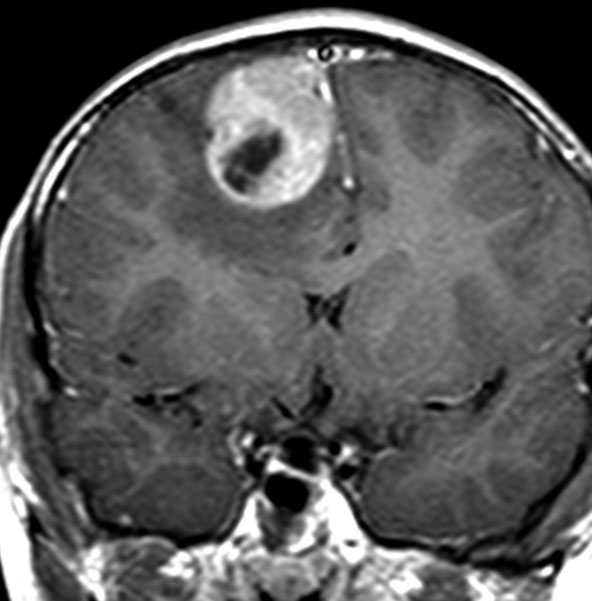

典型的な画像(膠芽腫に近い病理像の例)

特に悪性度の高かったPNETのMRI画像です。病理は膠芽腫に近い組織像でした。この子は4歳でした。小さい子供にできますが発見されたときには巨大な腫瘍になってしまっていることが多いです。この腫瘍の初回手術の時にはあふれるように出血しました。治療は,手術でなるべく全部取らないとなりません。でもこんなに大きいのを手術でいっぺんに取ると命が危ないし,摘出できても障害が大きくなりすぎますから,化学療法や放射線治療で小さくしておいてから,開頭手術で全部摘出するという方法もあります。この子供はそうしました。もし3歳以下だと放射線が使いにくいので化学療法だけになりますが,いずれにしてもPNETの治療は難しいです。

脳脊髄照射と化学療法で抑え込んで,右の写真は治療後10年経ったときのものです。大きくなってからは,高次脳機能障害と難治性てんかんで学校へ通うのが難しくなりました。